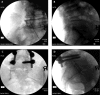

Figure 11.

Figure 11.. A, B, C and D, Radiofrequency of L5-S1 Level, AP and Lateral Views

Note the tangential angles of the needles and the L5 medial branch (dorsal ramus) ablation over the ala of the sacrum.